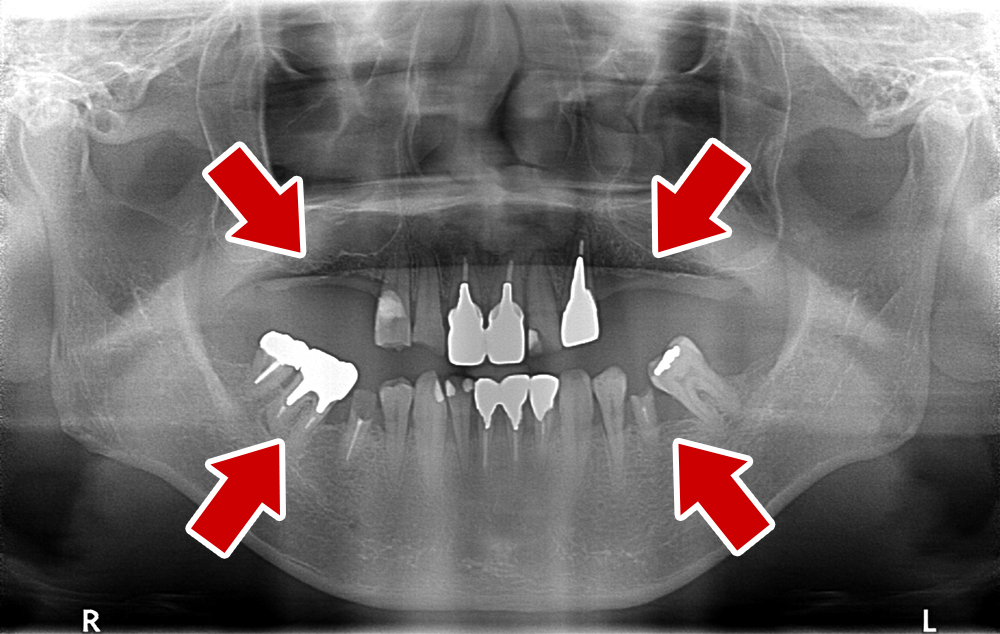

55歳 男性

- 主訴

- 前歯でしか咬めなく、食事を採るのに非常に困難で辛い

- 処置内容

- 上顎6本、下顎3本

- 治療費用

- 上顎:約230万(税込)下顎:約120万(税込)

- 治療期間

- 上顎:1年(仮歯まで8か月)下顎:8か月(仮歯まで5か月)

- リスク

- 上部構造物、仮歯の破折、術後の腫れ(3日)、人工歯根脱落リスクがあります